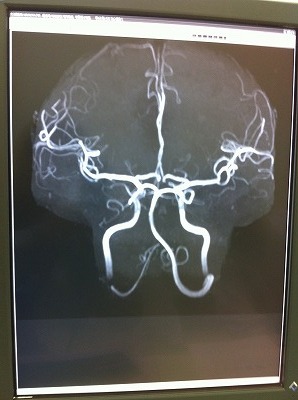

血管だけの映像が、立体的に映し出される。。。時々TVで見るやつだ。。。

動脈瘤などの、数ミリの瘤や、細く詰まっている箇所なども分かるのらしい。

大きな問題は無いとのことで、、ちょっと安心。